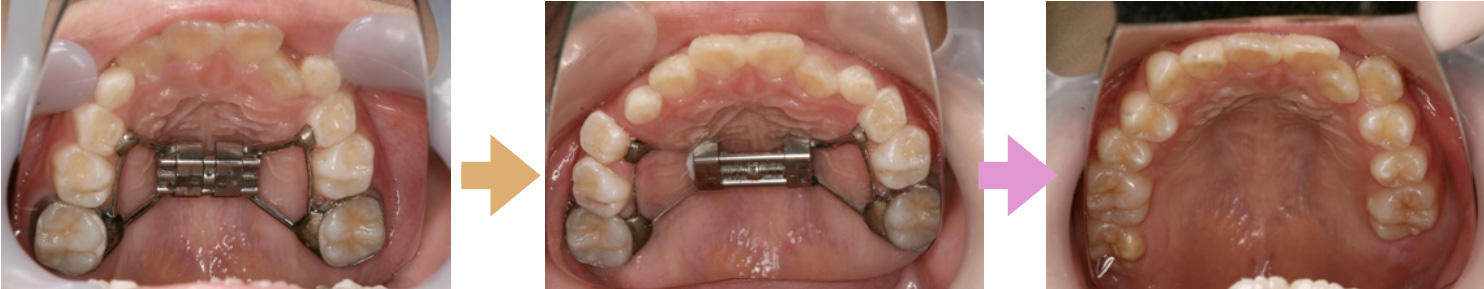

私が「もしかしたら」と思う理由は、11歳の時点で上顎を拡大することができたら、抜かずに済ん だかもしれません。上の写真は別の患者さんですが、左から右まで3年の月日が経過しています。 まだBRASS(矯正装置)を入れていないので、並びが不完全ですが、永久歯4本を守ることができ るのではないかと思います。一番右の写真は一番奥にもう1本第二大臼歯が生えると生えそろいま す。前ページの右の上顎の写真と比べて、横幅がゆったりしているのがわかりますか?前のページの 上顎は尖っていますよね。これは上顎が狭く、鼻呼吸がしにくい顔ということです。見た目だけなら ○でも全身のことを考えたらイマイチでしょう。全身の健康を第一に考える私が選ぶ方法は、今な ら「上顎の拡大」です。治療対象は第1大臼歯が完全に生えていて、全身の成長がある間です。女の 子の場合、一般に小学生の間、男の子は中2ぐらいまででしょう。 「非抜歯矯正」と言っても、全く抜かないワケじゃありませんので、あしからず。第3大臼歯(親 知らず)は顔を出す前でも積極的に抜きます。また、症例によっては上顎の第2大臼歯を抜いて、第 3大臼歯を生えさせて並べる場合もあります。結果的に第1小臼歯を抜かず、口の中に28本の永久歯 が残るようにしたいんです。(通常の抜歯矯正では24本の永久歯で完成することが多い)